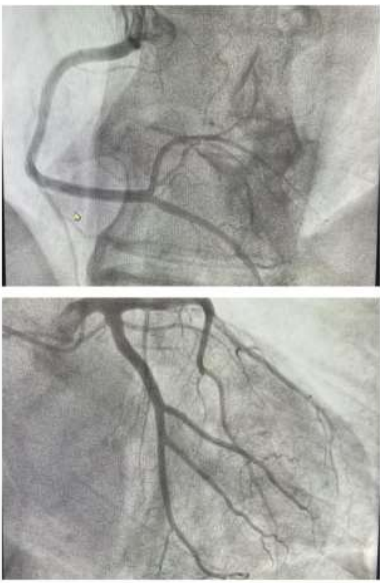

We report the case of a 57-year-old patient, known to have type 2 diabetes for 10 years on oral antidiabetics. The patient was initially admitted to the cardiology intensive care unit for predominantly left-sided congestive heart failure decompensated by a respiratory infection. The clinical examination found a conscious patient, hemodynamically stable, normotensive at 119/65 mmhg, tachycard at 110 beats/min, dyspneic with the presence of jugular vein turgor, edema of the lower limbs, crackling rales mid- fields. the neurological examination revealed a motor deficit in all 4 limbs, 3/5 proximally and 2/5 distally. The electrocardiogram showed a regular sinus rhythm at 105 beats/min, a normal heart axis, QRS at 110 ms, without secondary repolarization disorder. Chest x-ray revealed cardiomegaly, bilateral interstitial syndrome, and right basithoracic focus. A transthoracic echocardiography showed a dilated left ventricle, with an end-diastolic diameter of (58mm, indexed at 37mm/m2) (figure 1), global hypokinesia, severe left ventricular systolic dysfunction, with an ejection fraction of the left ventricle at 30%, moderate mitral regurgitation, left atrial dilatation, pulmonary arterial hypertension at 43 mmhg (figure 2), dilated lower vena cava not very compliant.

Figure 1: A transthoracic echocardiography showed a dilated left ventricle.